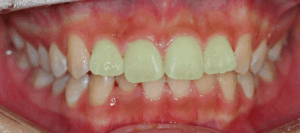

면목동 치과 틀어진 앞니(나비 치아)가 고민인 20대 환자, 상악골 확장 marpe 활용해 비발치 교정으로 도와드린 사례

안녕하세요^^ 글로리 김정은 대표 원장입니다. ​ 오늘은 많은 환자들께서 고민하고 계시는 부분인 "틀어진 앞니"에 대한 내용을 다뤄볼 예정인데요. ​ 저희 면목동 치과 에서는 어떠한 방법을 활용해 개선을 도와드렸는지에 대해 설명드리고…